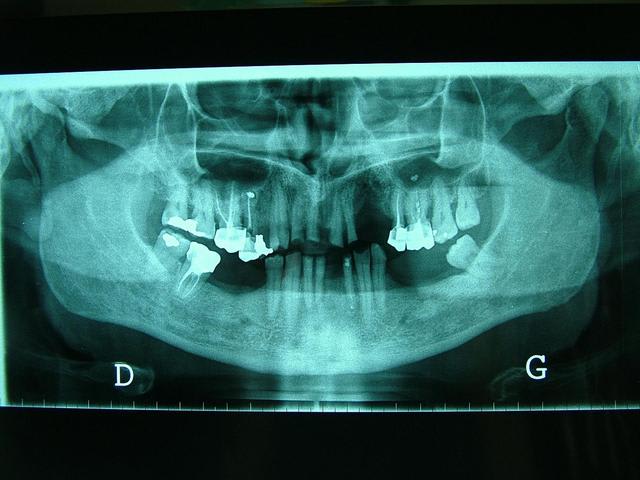

Photos jointes : un schéma à partir de la pano et des exemples clinique (pas exactement ton cas, mais pour te donner une idée du système).

Solene   pano   ingression vnhv91 - Eugenol

Solene   vis en tandem alb3ia - Eugenol

Solene   vis symphysaires athwrn - Eugenol

Pano xxztry - Eugenol